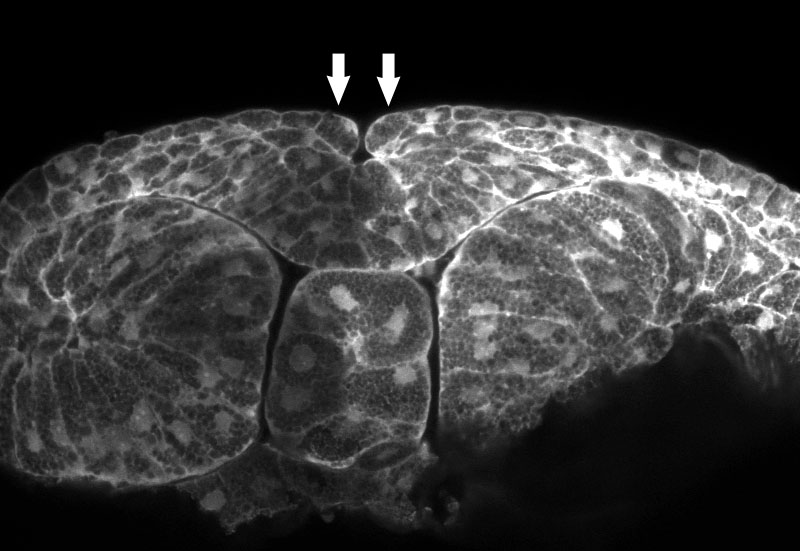

Figuur 3.

Sluiting van de neurale buis, Foto's, dwarsdoorsnede van kikkerembryos, 1 keer op de

kleine afbeelding klikken om het beeld uit te vergroten.

Deze foto's zijn met toestemming van Lance Davidson hier geplaatst.